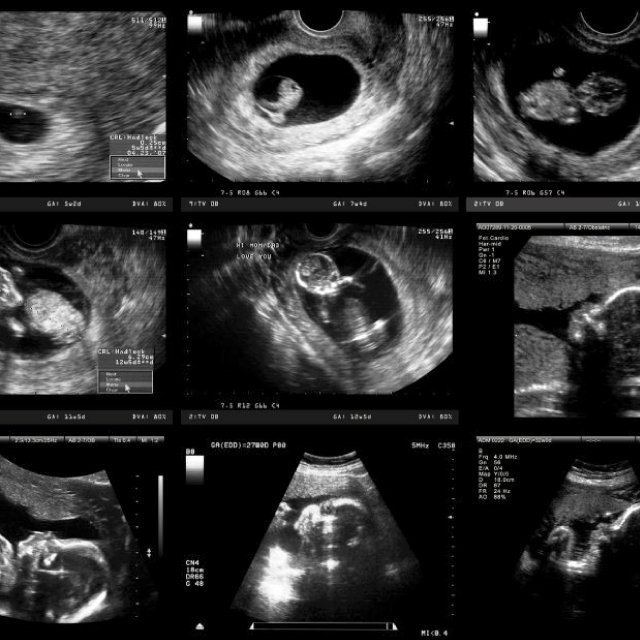

La ecografía transvaginal es un tipo de ecografía que se utiliza para examinar los órganos genitales de una mujer, incluyendo el útero, los ovarios, el cuello uterino y la vagina.

Se realiza a través de la vagina como su nombre indica ('trans' significa por o a través de) y durante la gestación suele ser el primer ultrasonido que se emplea para detectar o confirmar el embarazo.

Problemas que detecta el ultrasonido

- Embarazo ectópico, aquel que tiene lugar fuera de la matriz.

- Presencia de más de un feto (gemelos, trillizos, etc.).

- Aborto espontáneo o aborto natural.

- Placenta previa, cuando la placenta está insertada en la parte baja del útero.

- Desprendimiento de placenta.

- Problemas con el crecimiento del bebé o el nivel de líquido amniótico alrededor de éste.

- Cuello uterino corto, lo cual incrementa el riesgo de parto prematuro o aborto espontáneo tardío.

- Problemas estructurales en el bebé.

- Tumores del embarazo, incluyendo enfermedad trofoblástica gestacional.